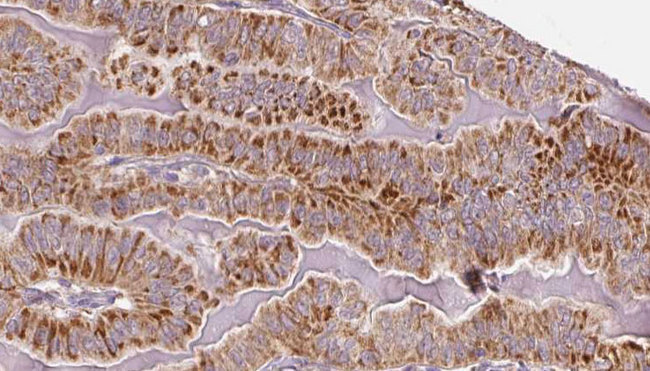

- Main image

- Experimental details

- 1:100 staining human thyroid carcinoma tissue by IHC-P. The sample was formaldehyde fixed and a heat mediated antigen retrieval step in citrate buffer was performed. The sample was then blocked and incubated with the antibody for 1.5 hours at 22°C. An HRP conjugated goat anti-rabbit antibody was used as the secondary.